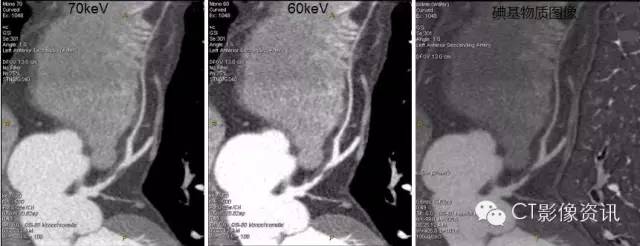

1、单能量工具 随着keV降低,VR图像血管细节显示更清楚,60keV更好的优化血管显示。

3、碘基物质图像观察 与低keV图像同样能清晰显示血管细节及软斑块内结构的密度差异。